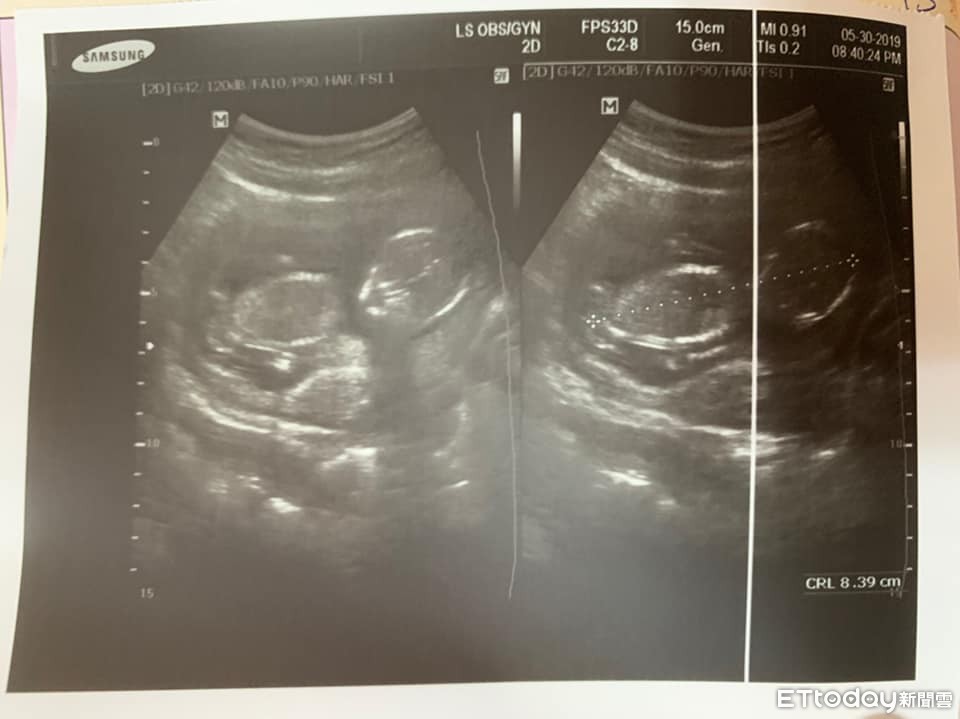

▲這是最近的產檢照片,醫生本來說那週可以看到,結果二寶不給看。(圖/原po授權引用)

雖然他認為,只要孩子平安健康,是男是女都好,不過還是比較希望有女兒,這樣就能湊成一個好字,「但很神奇的是,連產檢二寶都不給我們看,夾的非常緊,現在只能期待開獎那天了。」